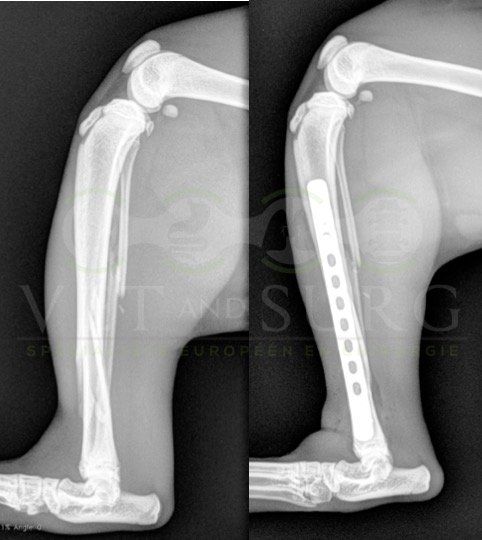

Fracture Salter-Harris sur un chaton Européen de 10 mois

Spike, chaton européen mâle de 10 mois, a été présenté en consultation pour boiterie du membre postérieur droit à la suite d'une chute depuis le 1er étage.

A la radiographie, une fracture de type Salter-harris 1 est diagnostiquée, avec déplacement de l'about discal.

Une réduction de la fracture par pose de 2 broches en croix a été réalisée.